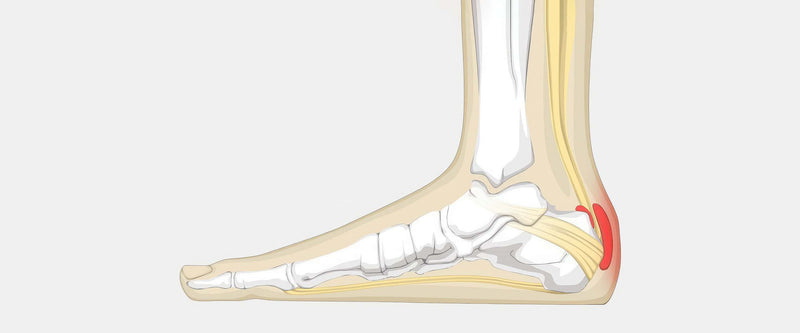

Achilles bursitis heel pads hot sale

Achilles bursitis heel pads hot sale, Achilles Heel Padded Sleeve Relieves Supports Tendonitis Injury ZenToes hot sale

Product code: Achilles bursitis heel pads hot salePexmen 2Pcs Pair Heel Cushions Cups for Achilles Bursitis Cracked Spur Foot Plantar Fasciitis Pain Relief Heel Protector Pads hot sale, TheraStep Achilles Heel Pad Silipos hot sale, Silipos Therastep Achilles Tendon Support Sleeve Algeos hot sale, Silipos Achilles Heel Pad Each hot sale, Amazon CRS Cross Achilles Heel Sleeve Pair of Premium Padded Compression Gel Sleeve Sock for Cushion Protection of Haglunds Bump Tendonitis Bursitis X Large Health Household hot sale, Bursitis of the Heel What is it Ultrasound Guided Injections hot sale, Achilles Bursitis Causes Symptoms Treatment hot sale, Achilles Heel Pad MyFootShop hot sale, Amazon Heel Cups Plantar Fasciitis Inserts Heel Pads Cushion 3 Pairs FSA or HSA eligible Great for Heel Pain Heal Dry Cracked Heels Achilles Tendinitis for Men Women. Gel Heel Cups hot sale, Welnove Heel Pads for Achilles Tendonitis Heel Spurs Plantar Fasciit Ginax Store hot sale, Welnove Heel Pads for Achilles Tendonitis Heel Spurs Plantar Fasciit Ginax Store hot sale, Achilles Bursitis Retrocalcaneal Bursitis Symptoms Causes Treatment hot sale, Heel Bursitis Demystified Symptoms and Solutions hot sale, Bunga Pads Achilles Healpad hot sale, Heel bursitis Causes and treatment Treat My Achilles hot sale, TheraStep Achilles Heel Pad Silipos hot sale, Silipos Achilles Heel Pad FootcareUK hot sale, Amazon Achilles Tendonitis Heel Protector Socks Welnove Achilles Tendon Support Compression Socks Gel Padded Sleeve for Cushion Protection of Bursitis Tendonitis Tenderness Dry Cracked Large Healt... hot sale, Retrocalcaneal and Achilles Bursitis Radiology Key hot sale, Amazon Bunga Pads Achilles Heel Pad Small Medium Health Household hot sale, Midpoint Insertional Achilles Tendonitis hot sale, Heel bursitis Causes and treatment Treat My Achilles hot sale, Pexmen 2Pcs Pair Heel Cushions Cups for Achilles Bursitis Cracked Spur Foot Plantar Fasciitis Pain Relief Heel Protector Pads hot sale, ZenToes Achilles Heel Protector Sleeve for Bursitis Tendonitis 1 Pair in El Salvador at USD 26 Rating 4.1 hot sale, Heel Pain Physio Labs hot sale, Heel Bursitis Cause Symptoms Treatment Exercise hot sale, Achilles Heel Padded Sleeve Relieves Supports Tendonitis Injury ZenToes hot sale, Health Personal Health Wellness Healthcare Devices Povihome Heel Cushions Protectors Plantar Fasciitis Inserts 1 5 Thick Silicone Heel Pads for Cracked Dry Achilles Heels Heel Pain Relief 3 Pairs hot sale, Understanding and Treating Retrocalcaneal Bursitis hot sale, Silipos Achilles Heel Sleeve heel tendon gel cushion hot sale, Silopad Achilles Heel Pad Kettering Surgical Appliances hot sale, Achilles Heel Padded Sleeve Relieves Supports Tendonitis Injury ZenToes hot sale, Achilles Bursitis The Complete Injury Guide Vive Health hot sale, Heel Bursitis vs Achilles Tendinitis Exam hot sale, Silopad Achilles Heel Pad Small Medium from Essential Aids hot sale.